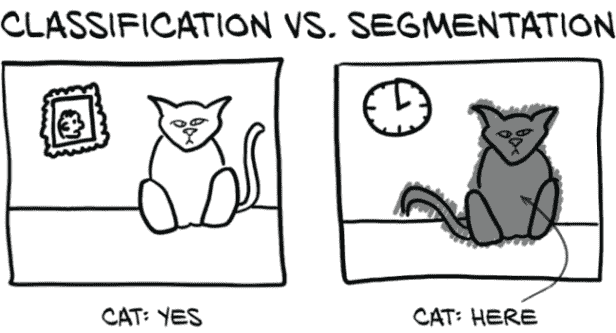

13.2 各种类型的分割

要开始,我们需要讨论不同类型的分割。对于这个项目,我们将使用语义分割,这是使用标签对图像中的每个像素进行分类的行为,就像我们在分类任务中看到的那样,例如,“熊”,“猫”,“狗”等。如果做得正确,这将导致明显的块或区域,表示诸如“所有这些像素都是猫的一部分”之类的事物。这采用标签掩模或热图的形式,用于识别感兴趣的区域。我们将有一个简单的二进制标签:真值将对应结节候选,假值表示无趣的健康组织。这部分满足了我们找到结节候选的需求,稍后我们将把它们馈送到我们的分类网络中。

13.3 语义分割:逐像素分类

通常,分割用于回答“这张图片中的猫在哪里?”这种问题。显然,大多数猫的图片,如图 13.3,其中有很多非猫的部分;背景中的桌子或墙壁,猫坐在上面的键盘,这种情况。能够说“这个像素是猫的一部分,这个像素是墙壁的一部分”需要基本不同的模型输出和不同的内部结构,与我们迄今为止使用的分类模型完全不同。分类可以告诉我们猫是否存在,而分割将告诉我们在哪里可以找到它。

图 13.3 分类结果产生一个或多个二进制标志,而分割产生一个掩码或热图。

如果您的项目需要区分近处猫和远处猫,或者左边的猫和右边的猫,那么分割可能是正确的方法。迄今为止我们实现的图像消费分类模型可以被看作是漏斗或放大镜,将大量像素聚焦到一个“点”(或者更准确地说,一组类别预测)中,如图 13.4 所示。分类模型提供的答案形式为“是的,这一大堆像素中有一只猫”,或者“不,这里没有猫”。当您不关心猫在哪里,只关心图像中是否有猫时,这是很好的。